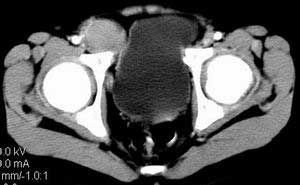

| 患者,男,9岁,因右下腹包块入院,血象不高,不规则发热,常超40度。 平扫: ![]() ![]() ![]() ![]() ![]() ![]() ![]() ![]() ![]() ![]() ![]() ![]() ![]() ![]() ![]() ![]() ![]() ![]() 增强: ![]() ![]() ![]() ![]() ![]() ![]() ![]() ![]() ![]() ![]() ![]() ![]() ![]() ![]() jiajie发言:骶椎右前区不规则软组织肿块,边缘光整,密度均匀,增强后均匀强化,右腹股沟区可见肿大淋巴结,临床有时发热,考虑淋巴瘤,儿童盆腔肿瘤应与神经母细胞瘤和横纹肌肉瘤鉴别。 longzhanghui发言:印象:盆腔右后壁不规则软组织肿块,并向前延伸.似为多个肿块融合,呈中等强化.初步考虑淋巴瘤. 听蝉观竹发言:右侧髂内、外组淋巴结肿大,从其形态和融合的情况看,同意大家意见-----考虑恶性病变,但是9岁男孩还要注意检查睾丸情况,有无隐睾? 常常类似情况是隐睾发生精原细胞瘤淋巴结转移,这个病例也要注意这一点!!! 广东凌发言:大家好,在这里我想说一下个人观点,我建议上传图片的同志能否辛苦一点就是把病史和图片都上传完整一点,比如这个病人的腹膜窗,并且这个病人的肠道的准备也是不怎么好,就从现有的质料看:病灶属于淋巴结肿大当无大的争议,有融合趋势,其内无坏死,边缘强化为主,故考虑:淋巴瘤!建议用腹膜窗看一下和肠道的关系! 阿圣发言:病灶属于淋巴结肿大当无大的争议,有融合趋势,其内无坏死,边缘强化为主,故考虑:淋巴瘤 结果是:淋巴瘤 病例来源:ct762。由宁静致远发布: http://www.radinet.com.cn/forum_view.asp?forum_id=4&view_id=2182 |